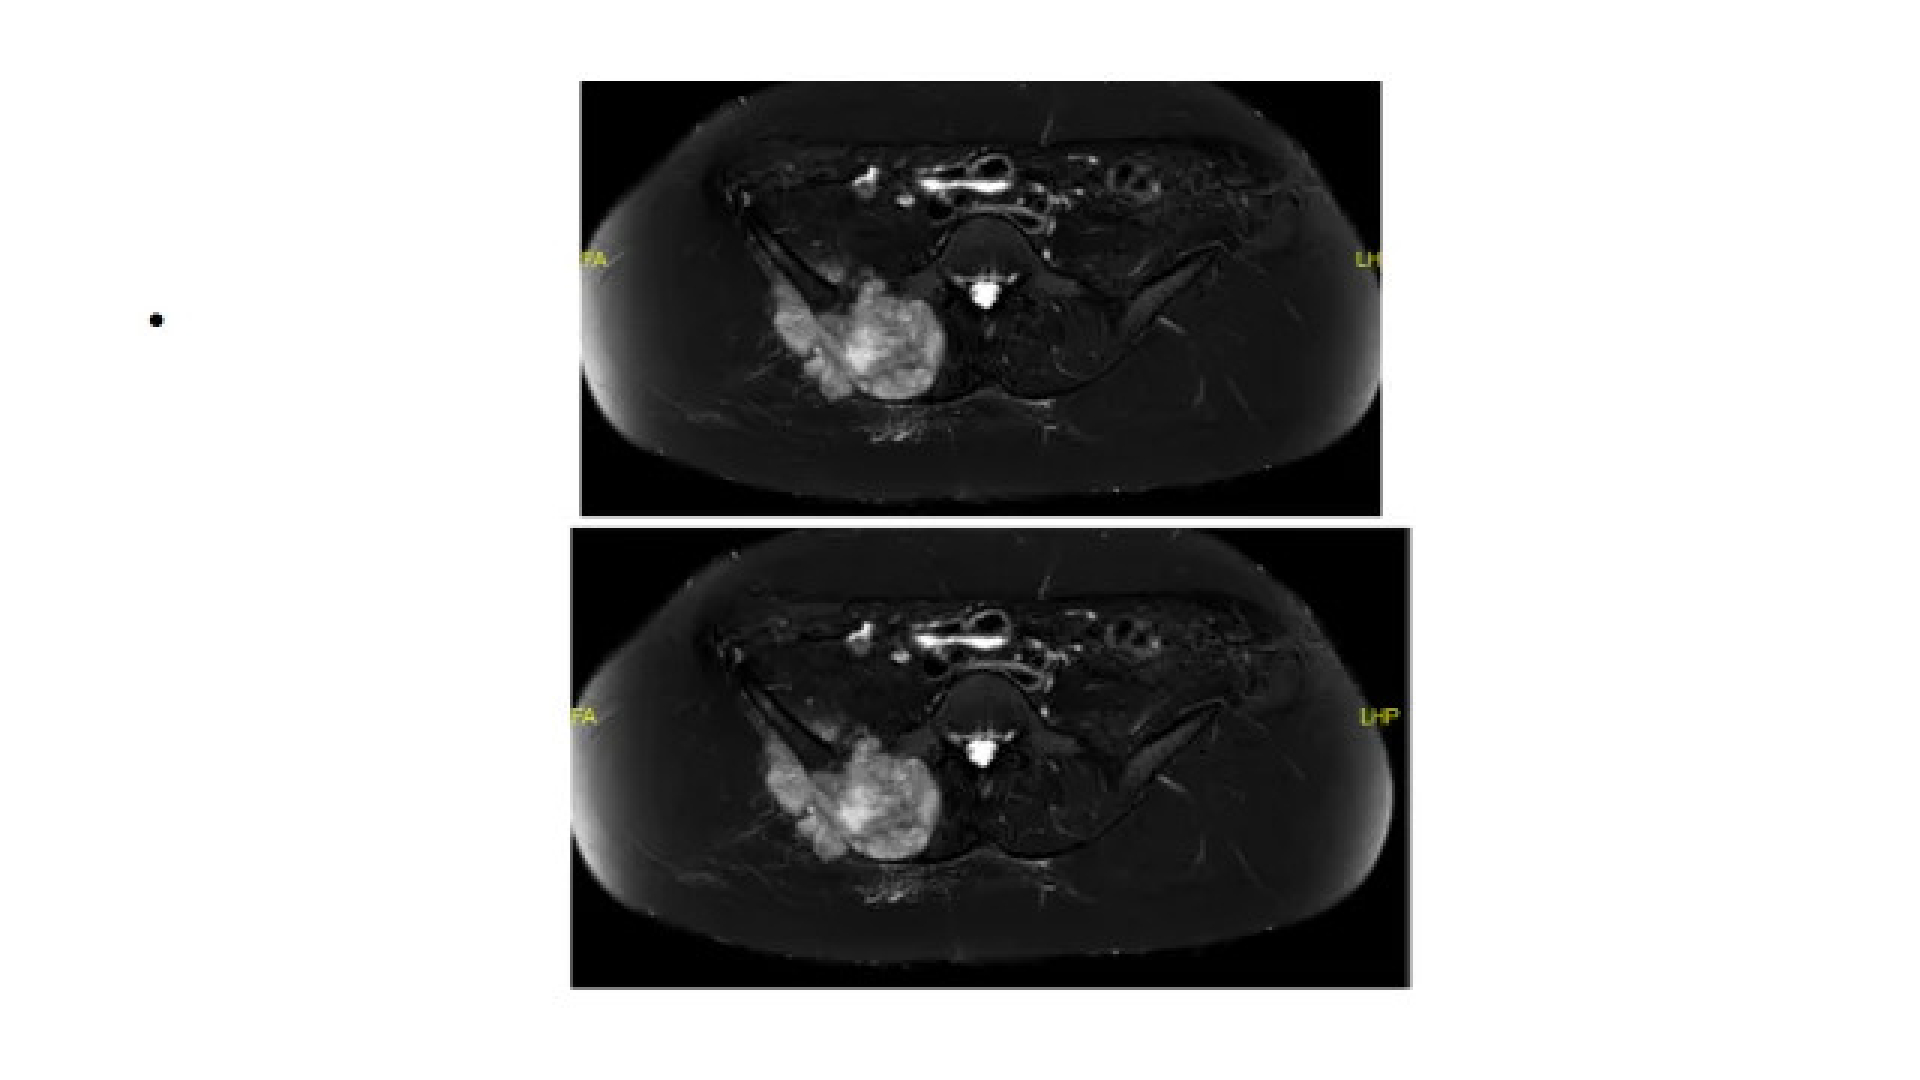

Ewing sarkomu osteosarkomdan sonra en sık görülen, küçük yuvarlak hücrelerden oluşan kötü diferansiye, yüksek dereceli ve kötü huylu bir kemik tümördür. En sık belirti ağrı ve şişliktir. Bazı hastalarda halsizlik ve ateş görülebilir. Cerrahi tedavisi konusunda uzmanlaşmış ortopedik onkoloji ekibi tarafından yapılmalıdır. Ayırıcı tanıda osteomiyelit (kemik iltihabı), lenfoma, mezenşimal kondrosarkom, küçük hücreli osteosarkom, metastatik nöroblastoma, akciğerin küçük hücreli karsinomu, embriyonel rabdomyosarkom ve eozinofilik granülom göz önünde bulundurulmalıdır.